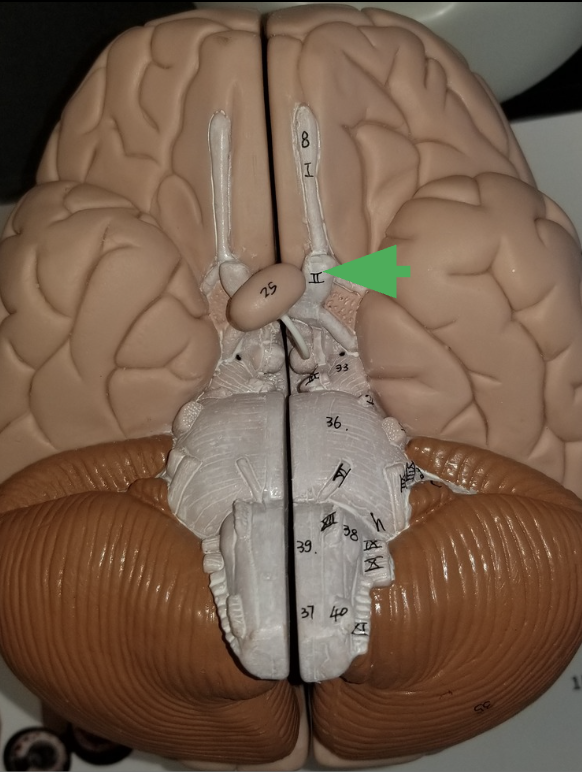

Optic Nerve (cranial nerve 2)

What does the optic nerve do?

carries axons from retina of the eye

what does the arrow indicate ?

Optic chiasm

What happens in the optic chiasm?

where some axons in each optic nerve cross over to the other side

What does the arrow indicate?

Optic Track

What does the optic track do?

carry axons from optic nerves ro the thalamus

What is the arrow pointing at?

Oculomotor nerve

What is the arrow indicating?

Trigeminal nerve (cranial nerve 5 /V )

What does the trigeminal nerve do?

Carries sensory information from the face

Carries motor commands to chewing muscles